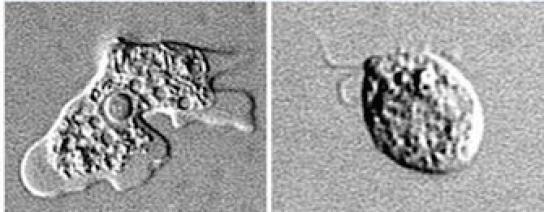

L’amibe est un animal unicellulaire vivant dans les eaux douces usées : lacs, piscines mal entretenues. L’espèce identifiée dans le sud des Etats-Unis est une amibe libre, nommée Naegleria fowleri. Elle est responsable de la méningo-encéphalite amibienne primitive (MEAP.)